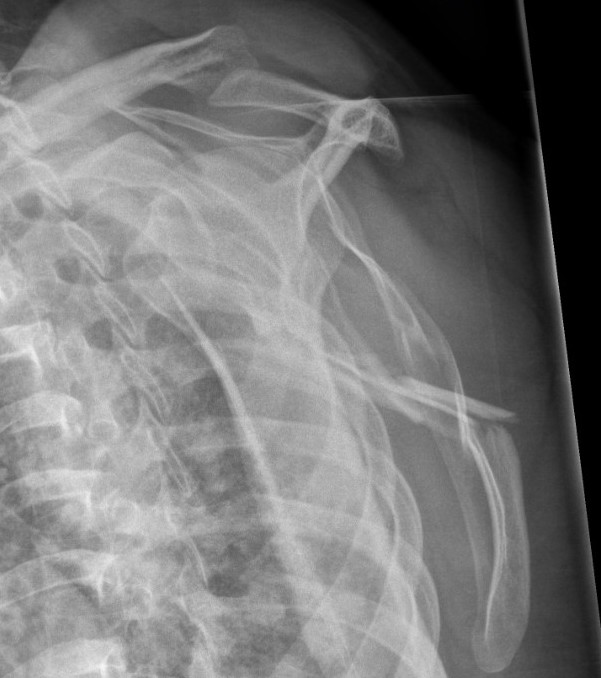

Angulation